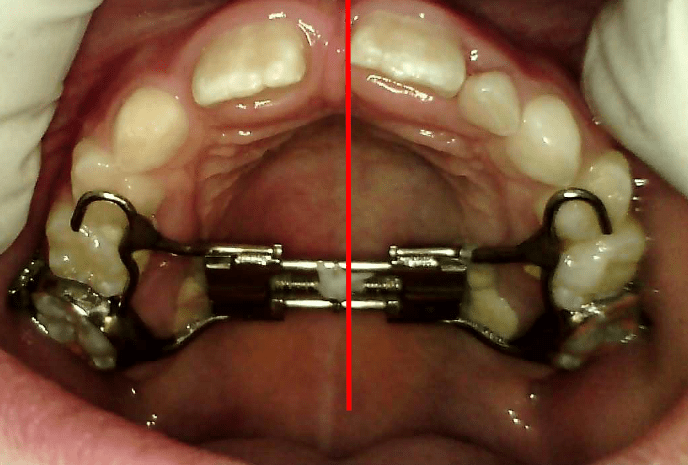

Here is a typical Rapid Maxillary Expander:

The RME appliance is a custom-made device that fits against the roof of the mouth and is attached to the upper molars using metal bands or acrylic supports. In the center of the appliance, there is a small screw (expansion screw) that is used to gradually widen the upper jaw.

- Daily Adjustments – A special key is provided to turn the expansion screw. The orthodontist will instruct you on how to do this at home.

- Turning the Screw – Usually, the screw is turned once or twice a day, depending on the treatment plan.

- Gentle Pressure – Each turn applies light pressure to separate the bones of the upper jaw.

- Visible Space – Within a few days or weeks, a small gap may appear between the two front teeth. This is normal and shows that the jaw is widening.